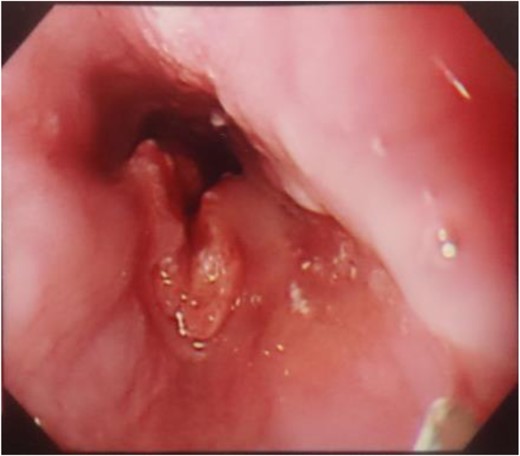

A 56-year-old man presented to our institution with esophageal and gastric cancer. Esophagogastroduodenoscopy (EGD) demonstrated a type 2 tumor occupying one-third of the circumference of the esophagus and measuring 28–33 cm from the incisors (Fig. 1). Endoscopy revealed that the tumor invaded the muscularis propria and biopsy revealed SCC. Moreover, a type 0-IIb tumor was located at the lesser curvature of the angle of the stomach. Endoscopy revealed invasion of the mucosa and biopsy revealed adenocarcinoma (Fig. 2). Computed tomography (CT) showed no enlarged lymph nodes in the mediastinum or distant metastasis in the liver or lung. Therefore, the patient underwent thoracoscopic esophagectomy (video-assisted thoracic surgery for esophagus), 2-field lymph node dissection, partial gastrectomy and gastric tube reconstruction via a retrosternal route for the advanced esophageal and early gastric cancers. Histopathologic analysis revealed Stage II (type 2, T3, ly2, v0, N0, PM0, DM0) esophageal and Stage I (type 0-IIb, T1, ly0, v0, N0) gastric cancer, with positive horizontal margins of dissection of the gastric cancer. Therefore, as additional treatment, we performed argon-plasma coagulation around the dissected gastric mucosa postoperatively.

A type 0-IIb tumor located at the lesser curvature of the angle of the stomach on esophagogastroduodenoscopy.